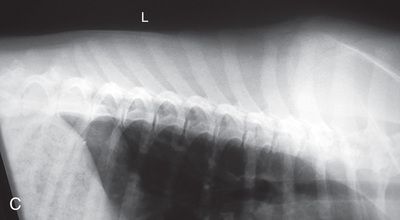

High-quality images are needed to see subtle changes in bone opacity, shape, and angulation of the vertebrae or vertebral column1,2 (Table 20.1). The common views of this portion of the axial skeleton are the lateral (L) and ventrodorsal (VD) views of the cervical, thoracic, thoracolumbar, lumbar, lumbosacral, sacral, and caudal vertebrae. Depending on the size of the patient, a full survey study is either four or five images of each orthogonal view.

Cat survey studies of the vertebrae are often part of the whole-body view. For both the dog and the cat, coned-down views are important for areas of interest. Dynamic views of the vertebrae are not common in cats but can be completed.